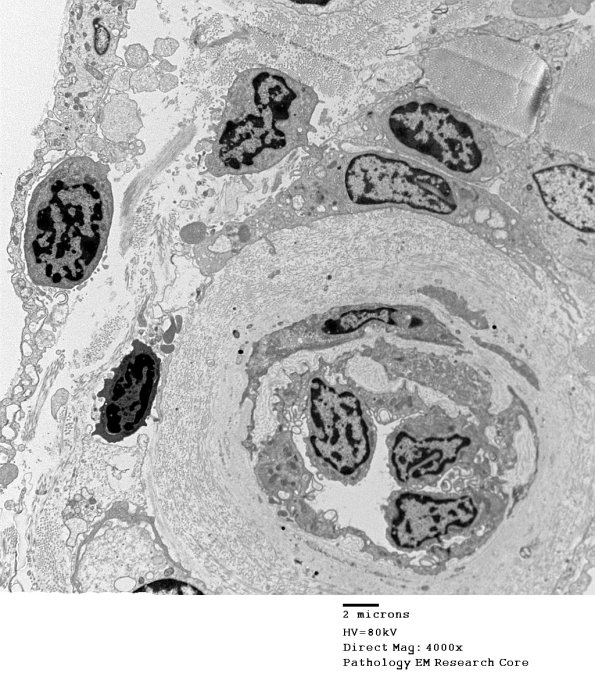

A small venule with adjacent perivascular inflammatory cells. Note the thickening of the vessel wall that likely reflects her diabetic status. (electron micrograph)